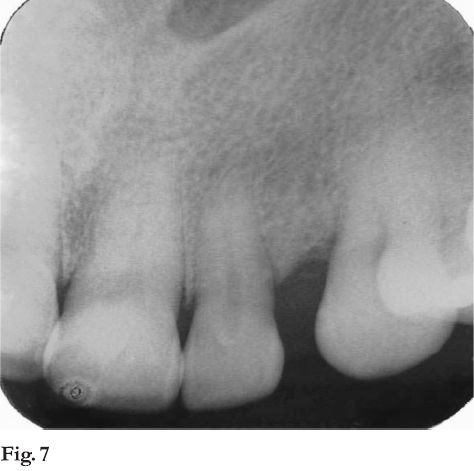

Al examen radiográfico se comprobó una erosión localizada de 2 mm; desplazamiento de las piezas 2.2 y 2.3 y a mesial de esta última se constata un defecto óseo vertical (fig. 7).

Diagnóstico clínico presuntivo: lesión hiperplásica reactiva. Se realiza biopsia incisional. Histopatológicamente debajo de mucosa pavimentosa crece una proliferación esencialmente fibromatosa caracterizada por presentar epitelio odontogénico en forma de largos cordones anastomosados entre si, adyacentes a material hialino, globular, con calcificación focal (fig. 8 y 9).